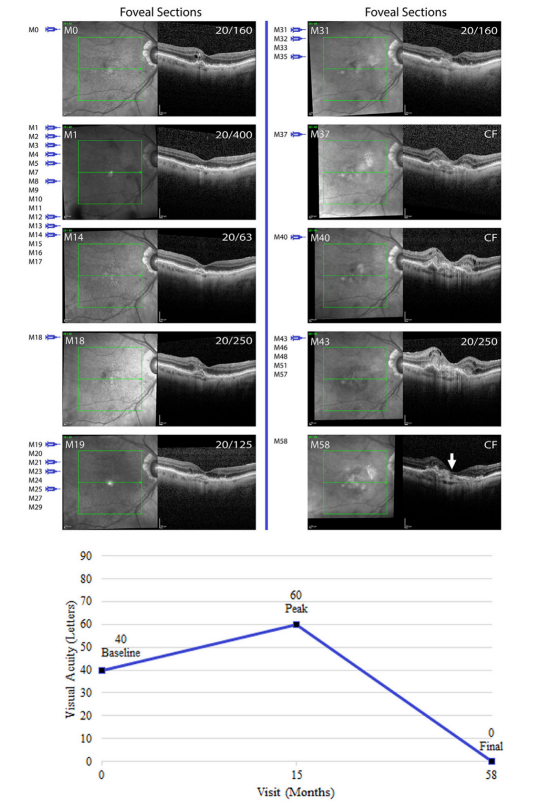

图 1 最后一次注射抗VEGF药物43个月后,血管性色素上皮脱离消退继发黄斑萎缩

Figure 1 Development of macular atrophy following collapse of a vascularized pigment epithelial detachment 43 months after the last anti-VEGF injection

8号受试者在血管性色素上皮脱离消退后出现中心凹下萎缩的经黄斑中心凹IR图像及SD-OCT图像。左上角表示随访时间(单位:月),右上角表示Snellen视力值,注射器符号(红色:阿柏西普)表示抗VEGF药物注射时间点,折线图显示基线视力、最佳视力及最终视力的字母数。

Infrared (IR) images and horizontal spectral domain optical coherence tomography (SD-OCT) scans through the fovea from subject 8 who developed subfoveal atrophy from regression of vascularized pigment epithelial detachment. Top left corner shows follow-up visits in months (M) and top right corner shows Snellen visual acuity. Injection symbols (red: aflibercept) show the visits at which anti-VEGF injection was administered. Line graph shows baseline, peak and final visual acuity in letters.